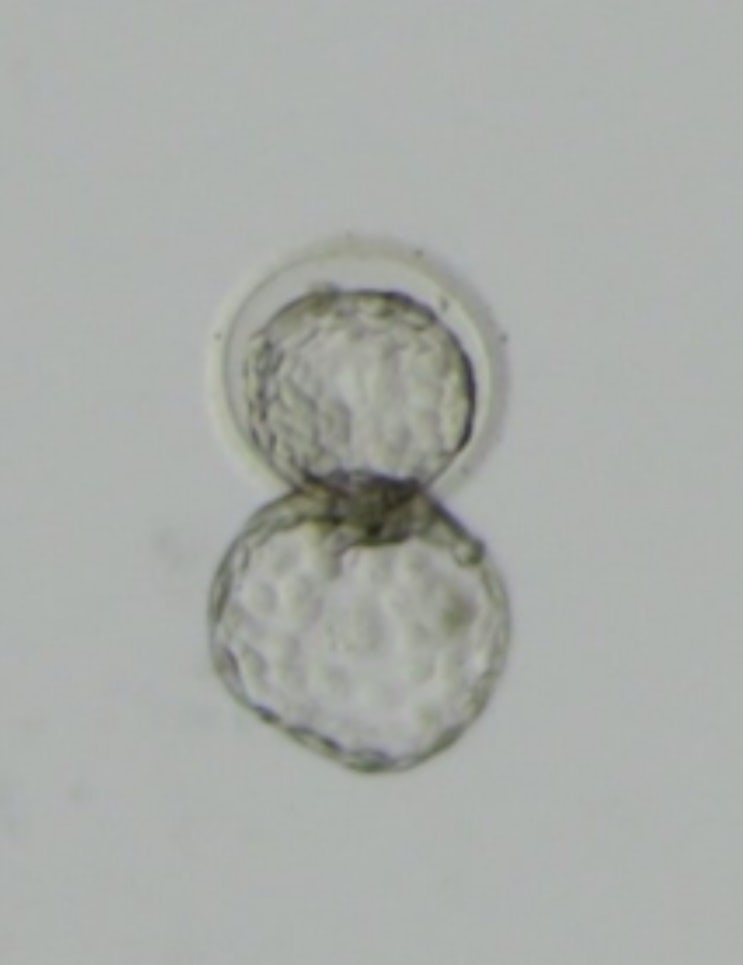

난임일기 EP 10 6일배양 눈사람배아 동결이식 배아이식 후 증상 음식 임테기 (10일 증상놀이)

6일배양 눈사람배아 동결이식 배아이식 후 증상 음식 임테기 10일 임신 증상놀이 인터넷에 알려져있는 이식...